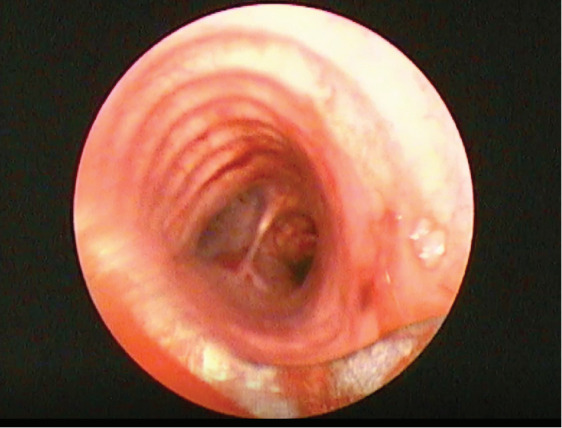

Endobronchial solitary papillomas are extremely rare lung neoplasms originating from the bronchial surface epithelium. They often present with cough or recurrent hemoptysis. These tumors are benign, but they should be followed closely because they may even have a low probability of malignant transformation features. It should be kept in mind that malignancy may develop especially if the patient is a smoker. Although the etiology is not known for certain, it is thought to be caused by human papillomavirus in some cases. A 43-year-old male patient was admitted with a complaint of chronic cough. Rigid bronchoscopy was performed for diagnostic and therapeutic purposes after imaging techniques revealed a lesion obstructing the lumen of the right main bronchus. The pathology result was reported as mixed bronchial papilloma. We aimed to present our case because of its rarity and to indicate that chronic cough must be further evaluated.

Abstract Image